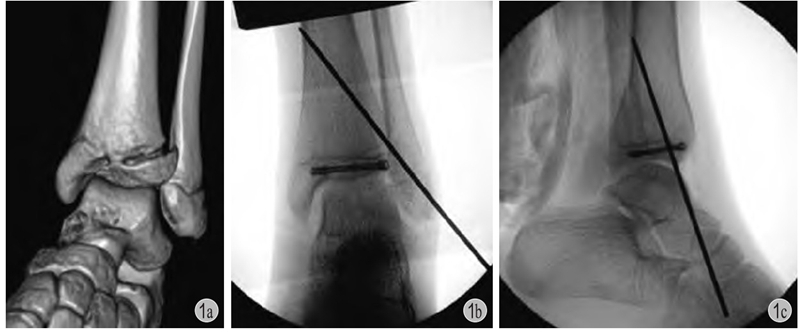

图2 患儿 男 11岁

a:右胫骨远端骨骺骨折(Salter-HarrisⅡ型)合并腓骨远端骨折;b:闭合复位,胫骨远端6枚克氏针贯通骺板固定;c:术后4个月见右小腿远端红肿,流脓;d:愈合后出现胫骨远端骺板早闭(星号)+局部皮质骨坏死(箭头)+慢性骨髓炎形成